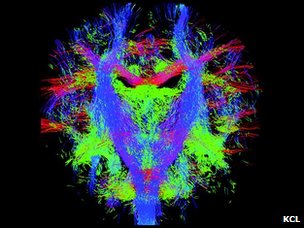

新生儿的脑神经纤维束

伦敦大学国王学院、帝国理工大学和牛津大学附属医院的儿科专家们的“制图”目标是希望能精确地、动态地图解脑神经信息传递线路和流程,在最细微具体的层次显示脑神经系统的发育成型过程。

这项研究的核心是MRI扫描技术的更新,使得科学家得以精确捕捉以前力所难及的胎儿脑神经系统成长的细节。